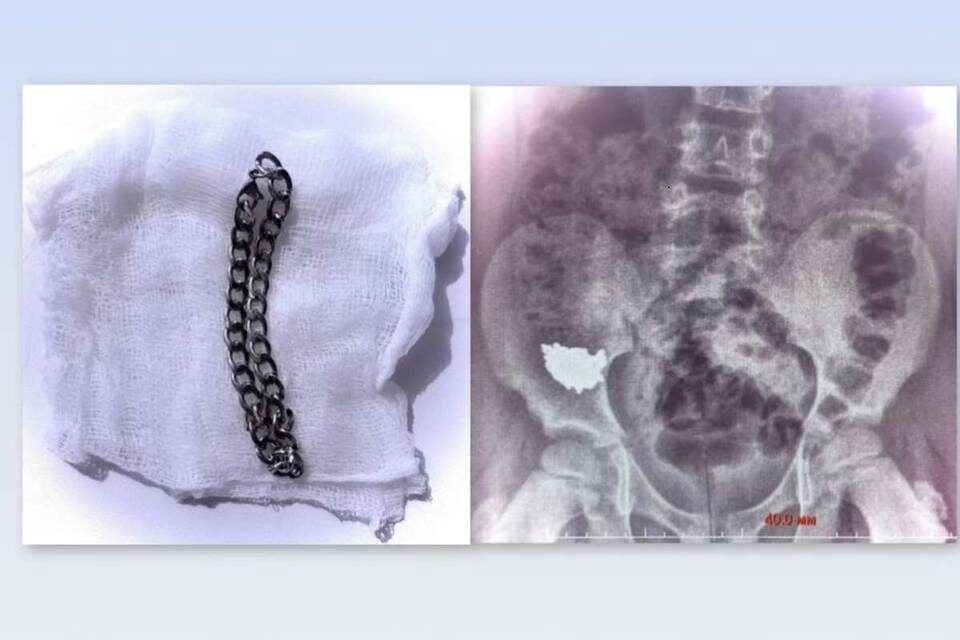

Врачи достали из живота школьника 20-сантиметровую цепь

В больницу юного воронежца доставили родители. В Воронеже во время игры школьник начальных классов проглотил 20-сантиметровую цепочку. О случившемся сообщают журналисты "Обозреватель.Врн". Сразу же после инцидента родители ребенка доставили его в больницу. Проведенный рентген показал, что украшение застряло внизу живота. Первые дни врачи наблюдали за школьников, проводя консервативное лечение. Однако снимки, сделанные на третьи и четвертые сутки, показали - инородное тело не двигается, оно словно застряло в кишечнике. Так как имелся высокий риск образования отверстия в органе, было решено экстренно провести операцию Сначала юному пациенту под общим наркозом провели колоноскопию, но цепочку в толстой кишке не обнаружили. Затем хирурги провели ревизию в брюшной полости, обнаружили украшение и извлекли его через просвет аппендикса. Операцию завершили удалением червеобразного отростка.

Школьник идет на поправку, врачи готовят его к выписке. МЧС: 5 пожаров за сутки в Волгоградской области